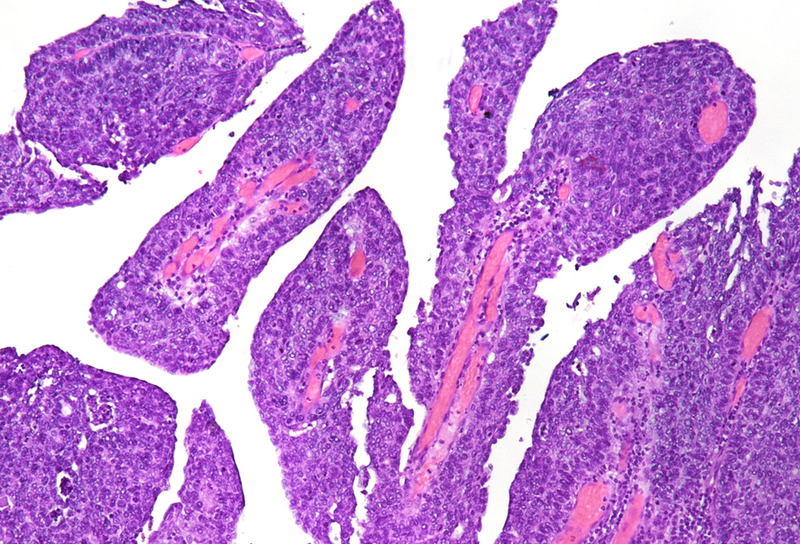

Histological examination showed a solid neoplasm with a predominantly nodular to lobulated growth pattern, frequently exhibiting peripheral palisading and central areas of comedonecrosis, located in the anal transitional zone (Panel A). The neoplastic cells were small to medium-sized, with scant cytoplasm, hyperchromatic nuclei, and inconspicuous nucleoli (Panel B). Glandular differentiation was minimal to absent (Panel C). The lesion showed focal connection with the overlying surface epithelium, which exhibited areas of papillary architecture with downward extension of neoplastic nests into the underlying stroma (Panel D).  The overall morphological features were consistent with a poorly differentiated carcinoma, not clearly indicating glandular and/or squamous differentiation.